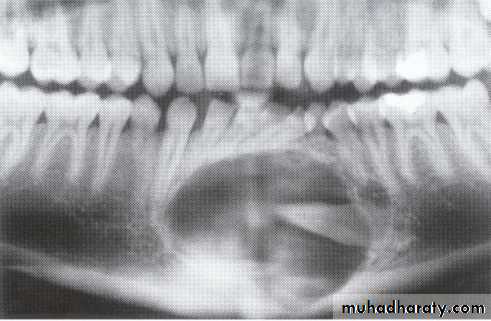

Ameloblasoma

*Non-metastasizing tumor originating from remnants of the odontogenic epithelium of the enamel organ or dental lamina. *Associated with the crown of impacted teeth.*80% located in the bicuspid & molar regions.

*Shape: is either unicystic or soap bubble-like lesion, Expansile, *Tooth migration is common,teeth in the area are vital.

*Adjacent teeth displaced, loosened,often resorbed

Extensive expansion in all dimensions

Maxillary lesions can extend into the paranasal sinuses, orbit or base of the skull.

Male > female. Age; > 30 years